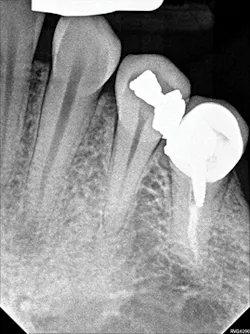

Figure 2: A periapical radiograph showing a suspicious area (i.e., radiolucency) approximating the apex of tooth No. 20, as well as the defective distal occlusal restoration on tooth No. 21

Figure 3: A periapical radiograph showing tooth No. 22 with a radiolucency near the apex, which looked small relative to the areas on Nos. 20 and 21. There is also distortion of the appearance of the mental foramen in the area.